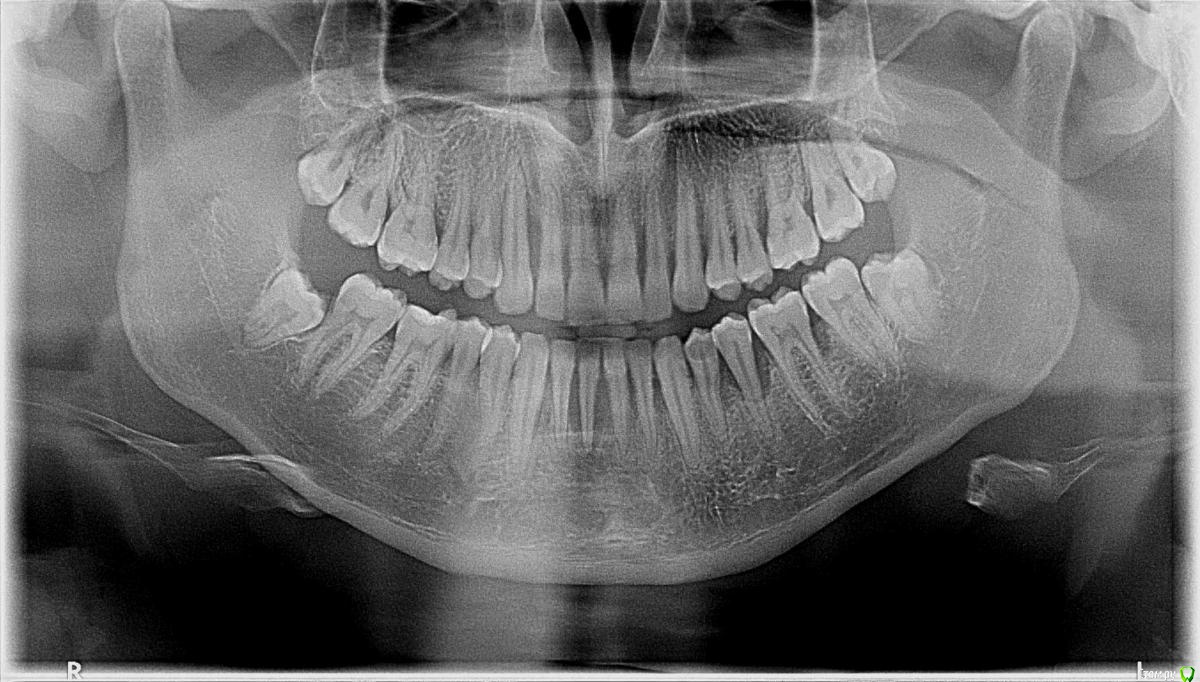

Paggy Опубликовано 17 декабря, 2019 Поделиться Опубликовано 17 декабря, 2019 ЗдравствуйтеПришел в клинику с жалобами на несколько шатающихся зубов (один нижний и верхние), чувствительность десен и появившийся запах изо рта. Сделали проф гигиену, прописали ципрофлоксацин на 5 дней. Обозначили лечение - открытый кюретаж, потом шинирование верхних и нижних зубов. Проконсультировался еще у одного парадонтолога. На вопрос можно ли восстановить десны и спасти шатающиеся зубы, врач ответил, что сначала нужно остановить инфекцию, которая разрушает ткань, а шатающийся нижний уже не спасти. Отправил сдавать кровь на гликированный гемоглобин и общий анализ с лейкоцитарной формулой. На январь назначил гигиену, закрытый кюретаж, введение лекарств в карманы. Дальше сказал, будем смотреть, что делать.Диагноз ни от одного, ни от второго врача не услышал, понял только что все плохо. Можно по этому снимку определить что у меня? Какое лечение необходимо и что можно сделать с теми зубами, которые шатаются? Ссылка на комментарий

ЛанаМ Опубликовано 18 декабря, 2019 Поделиться Опубликовано 18 декабря, 2019 Диагноз - парадонтит. План лечения правильный. Еще бы консультацию ортопеда по поводу прикуса и наличия суперконтактов. Ссылка на комментарий

ЛанаМ Опубликовано 19 декабря, 2019 Поделиться Опубликовано 19 декабря, 2019 Первым делом купируется воспалительный процесс, в вашем случае это ципрофлоксацин, и проводится удаление зубных отложений. Затем кюретаж (открытый или закрытый это нужно определять на очном осмотре). Вы сдали анализы, чтобы определить,какие процессы в организме привели к такой ситуации. Также может быть необходимо шинирование, удаление нежизнеспособных зубов, протезирование. Пародонтит - это заболевание на всю оставшуюся жизнь. Раз в полгода, а может быть и чаще или реже, вам нужно будет проходить курс поддерживающей терапии, чтобы заболевание не прогрессировало. Поэтому выбирайте врача с которым будете работать долгие годы. Ссылка на комментарий